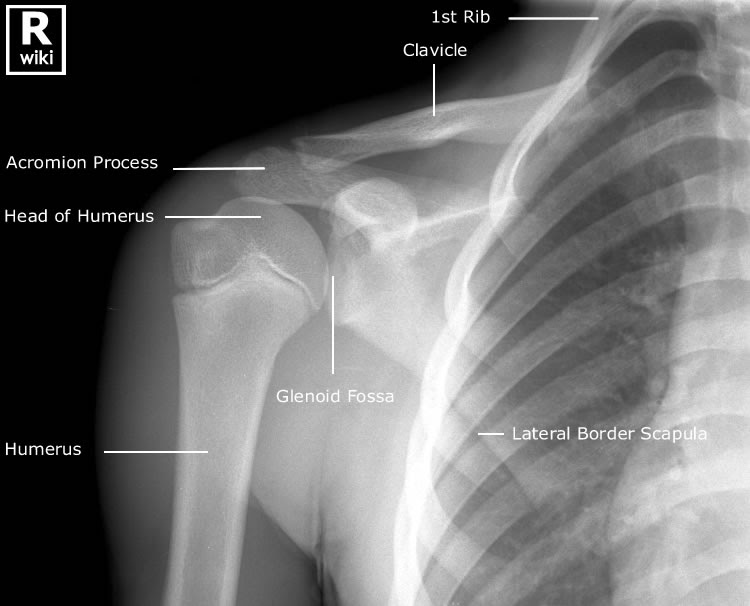

Shoulder X Ray 11 Year Old . A fever is variably present. Bickle i, worsley c, tan w, et al. Our comprehensive guide will teach you the abcd approach and. Diagnosis is confirmed with plain radiographs of the shoulder. Older children present with pain, dysfunction,. Infection, clavicle fracture, shoulder dislocation, and brachial plexus injury must be ruled out. The anteroposterior shoulder view in pediatrics is part of a two view series examining the shoulder joint, clavicle, scapula and proximal humerus. Treatment is usually nonoperative in younger patients due to the remodeling potential of the proximal. Reference article, radiopaedia.org (accessed on 18 oct.